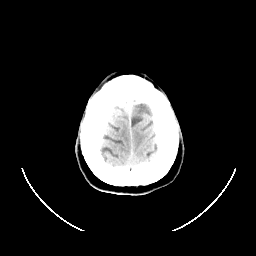

CT Study #1 -- Slice #27

[Home][Help][Clinical][Tour 1] Slice 27